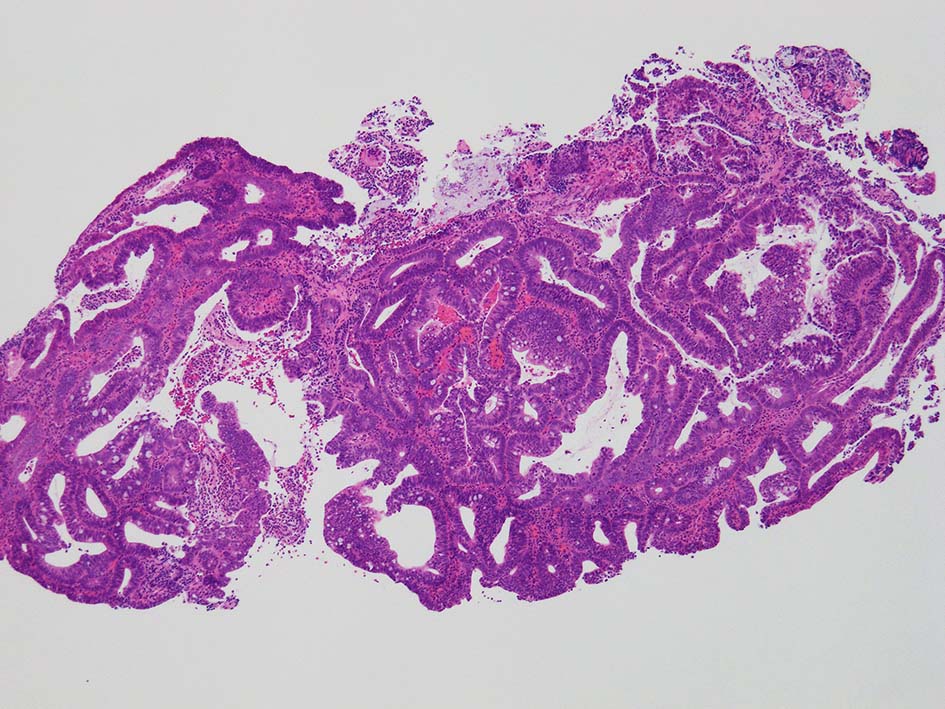

腸管型の腺癌。大腸の高分化腺癌と組織学的に区別は難しい.

desmoplastic fibrosis, 粘液浸潤のみられる組織片にはsig, porのadenocarcinoma浸潤が確認される.